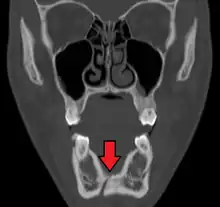

| 3D computed tomographic image of a mandible fracture in two places. One is a displaced right angle fracture and the other is a left parasymphyseal fracture. | |

Computed tomography is the most sensitive and specific of the imaging techniques. The facial bones can be visualized as slices through the skeletal in either the axial, coronal or sagittal planes. Images can be reconstructed into a 3-dimensional view, to give a better sense of the displacement of various fragments. 3D reconstruction, however, can mask smaller fractures owing to volume averaging, scatter artifact and surrounding structures simply blocking the view of underlying areas.